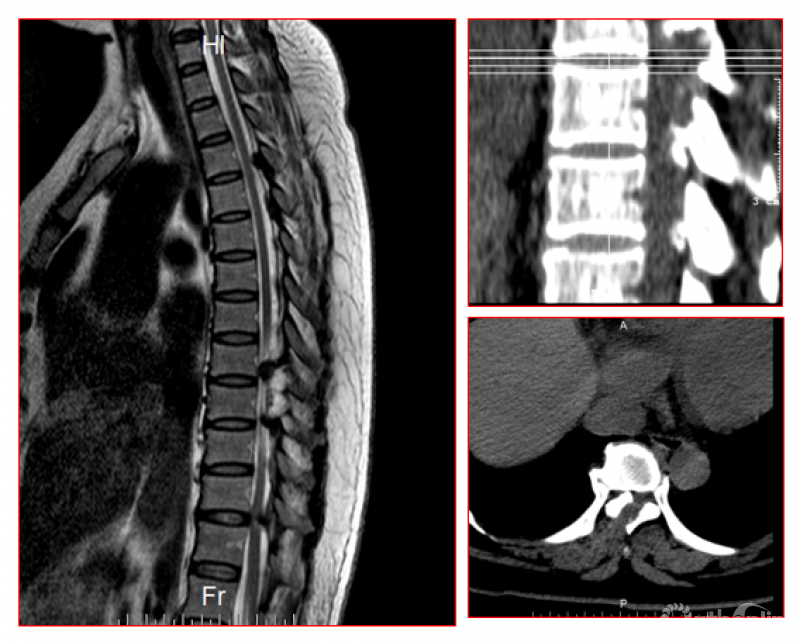

脊柱内镜手术通常作为首选手术方法,能有效地减压并进行相应的处理。适用于胸椎管狭窄症,如胸椎黄韧带肥厚症、胸椎间盘突出症、胸椎后纵韧带骨化症等,尤其适合单节段狭窄者。

1.胸椎结核:在脊柱内镜下进行穿刺及置管引流等;

2.胸椎椎管内囊肿:在脊柱内镜下进行病病灶切除术等;

3.胸椎后纵韧带骨化、骨水泥渗漏等;